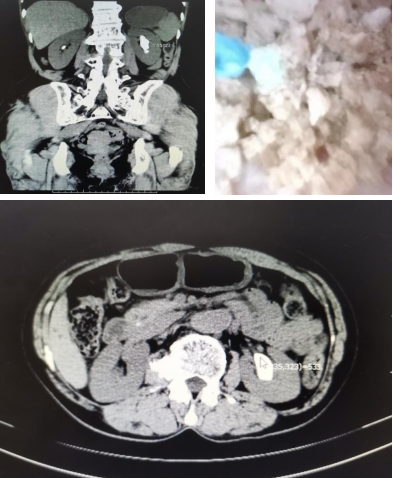

1個月前,陳姨因右側(cè)腰腹部疼痛來到我院泌尿外科就診,經(jīng)接診醫(yī)師詳細詢問病史,結(jié)合檢查結(jié)果明確診斷為雙腎多發(fā)結(jié)石,其中左腎結(jié)石較大,最長徑達3.6cm。

周雄主任帶領泌尿外科團隊根據(jù)陳阿姨的檢查結(jié)果及臨床診斷認真分析,決定采用輸尿管軟鏡鈥激光碎石為陳阿姨解決病痛。該術式無需開刀,也無需腰上打洞,通過人體自然腔道:尿道、膀胱、輸尿管逆行入腎,找到結(jié)石,鈥激光粉碎結(jié)石,無傷口,基本無出血。

經(jīng)過充分的術前準備后,周雄團隊為陳阿姨成功實施了經(jīng)尿道輸尿管軟鏡鈥激光碎石術,手術時間控制在80分鐘以內(nèi),避免了感染等并發(fā)癥的出現(xiàn)。由于創(chuàng)傷極小,陳阿姨很快便康復出院了。